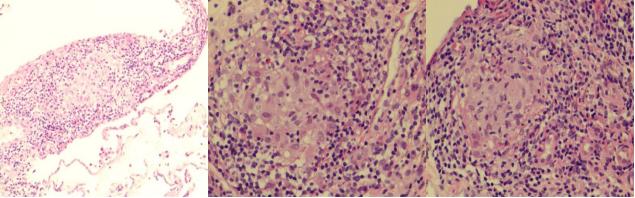

肺组织病理结果:

(右下叶背段)送检肺组织,肺泡腔内见少许组织细胞渗出,部分间质增宽,个别淋巴细胞浸润,碳尘沉着,局灶可见一些组织细胞聚集, 组织改变为肺间质性炎症,未见肉芽肿及肿瘤。

免疫组化结果:CK(上皮+),LCA(CD45)(-),CD163(组织细胞+);

特殊染色结果:AB(-),抗酸(-),PAS(-),GMS(-)。

肺组织病理:

顾莹莹 教授解读:

右下肺基底段的活检,见大量淋巴细胞浸润,夹杂浆细胞,但未见明确中性粒细胞,考虑慢性炎症性细胞浸润,可见多个边界清楚的肉芽肿性病灶及多核巨细胞,小血管上未见明确血管炎改变,肉芽肿病灶未见坏死表现,以类上皮细胞为主,散在多核巨细胞,周围未见纤维组织包裹,要考虑鉴别感染与非感染性肉芽肿。该患者背景可见炎症细胞浸润,首先考虑感染,但抗酸及六胺银染色均为阴性。隐球菌可导致肉芽肿性改变,但往往比较散在,以多核巨细胞为主,多核巨细胞内常可见吞噬隐球菌孢子,该患者肉芽肿比较紧密。结节病不会出现坏死,周围可见纤维母细胞包裹,背景淋巴细胞不多,亦不会出现咯血症状,大多数患者为体检发现,影像学可见纵隔及双肺淋巴结改变,该患者不符合。患者肺泡腔未见机化,肺组织未见肿瘤及血管炎改变,整体看考虑感染可能性大,重点排查分枝杆菌,增值性结核可见肉芽肿性改变,但往往可见朗格汉斯细胞,该患者以多核巨细胞为主,考虑非结核分枝杆菌感染可能性大。

肺组织病理:组织改变为慢性支气管炎伴曲霉感染。